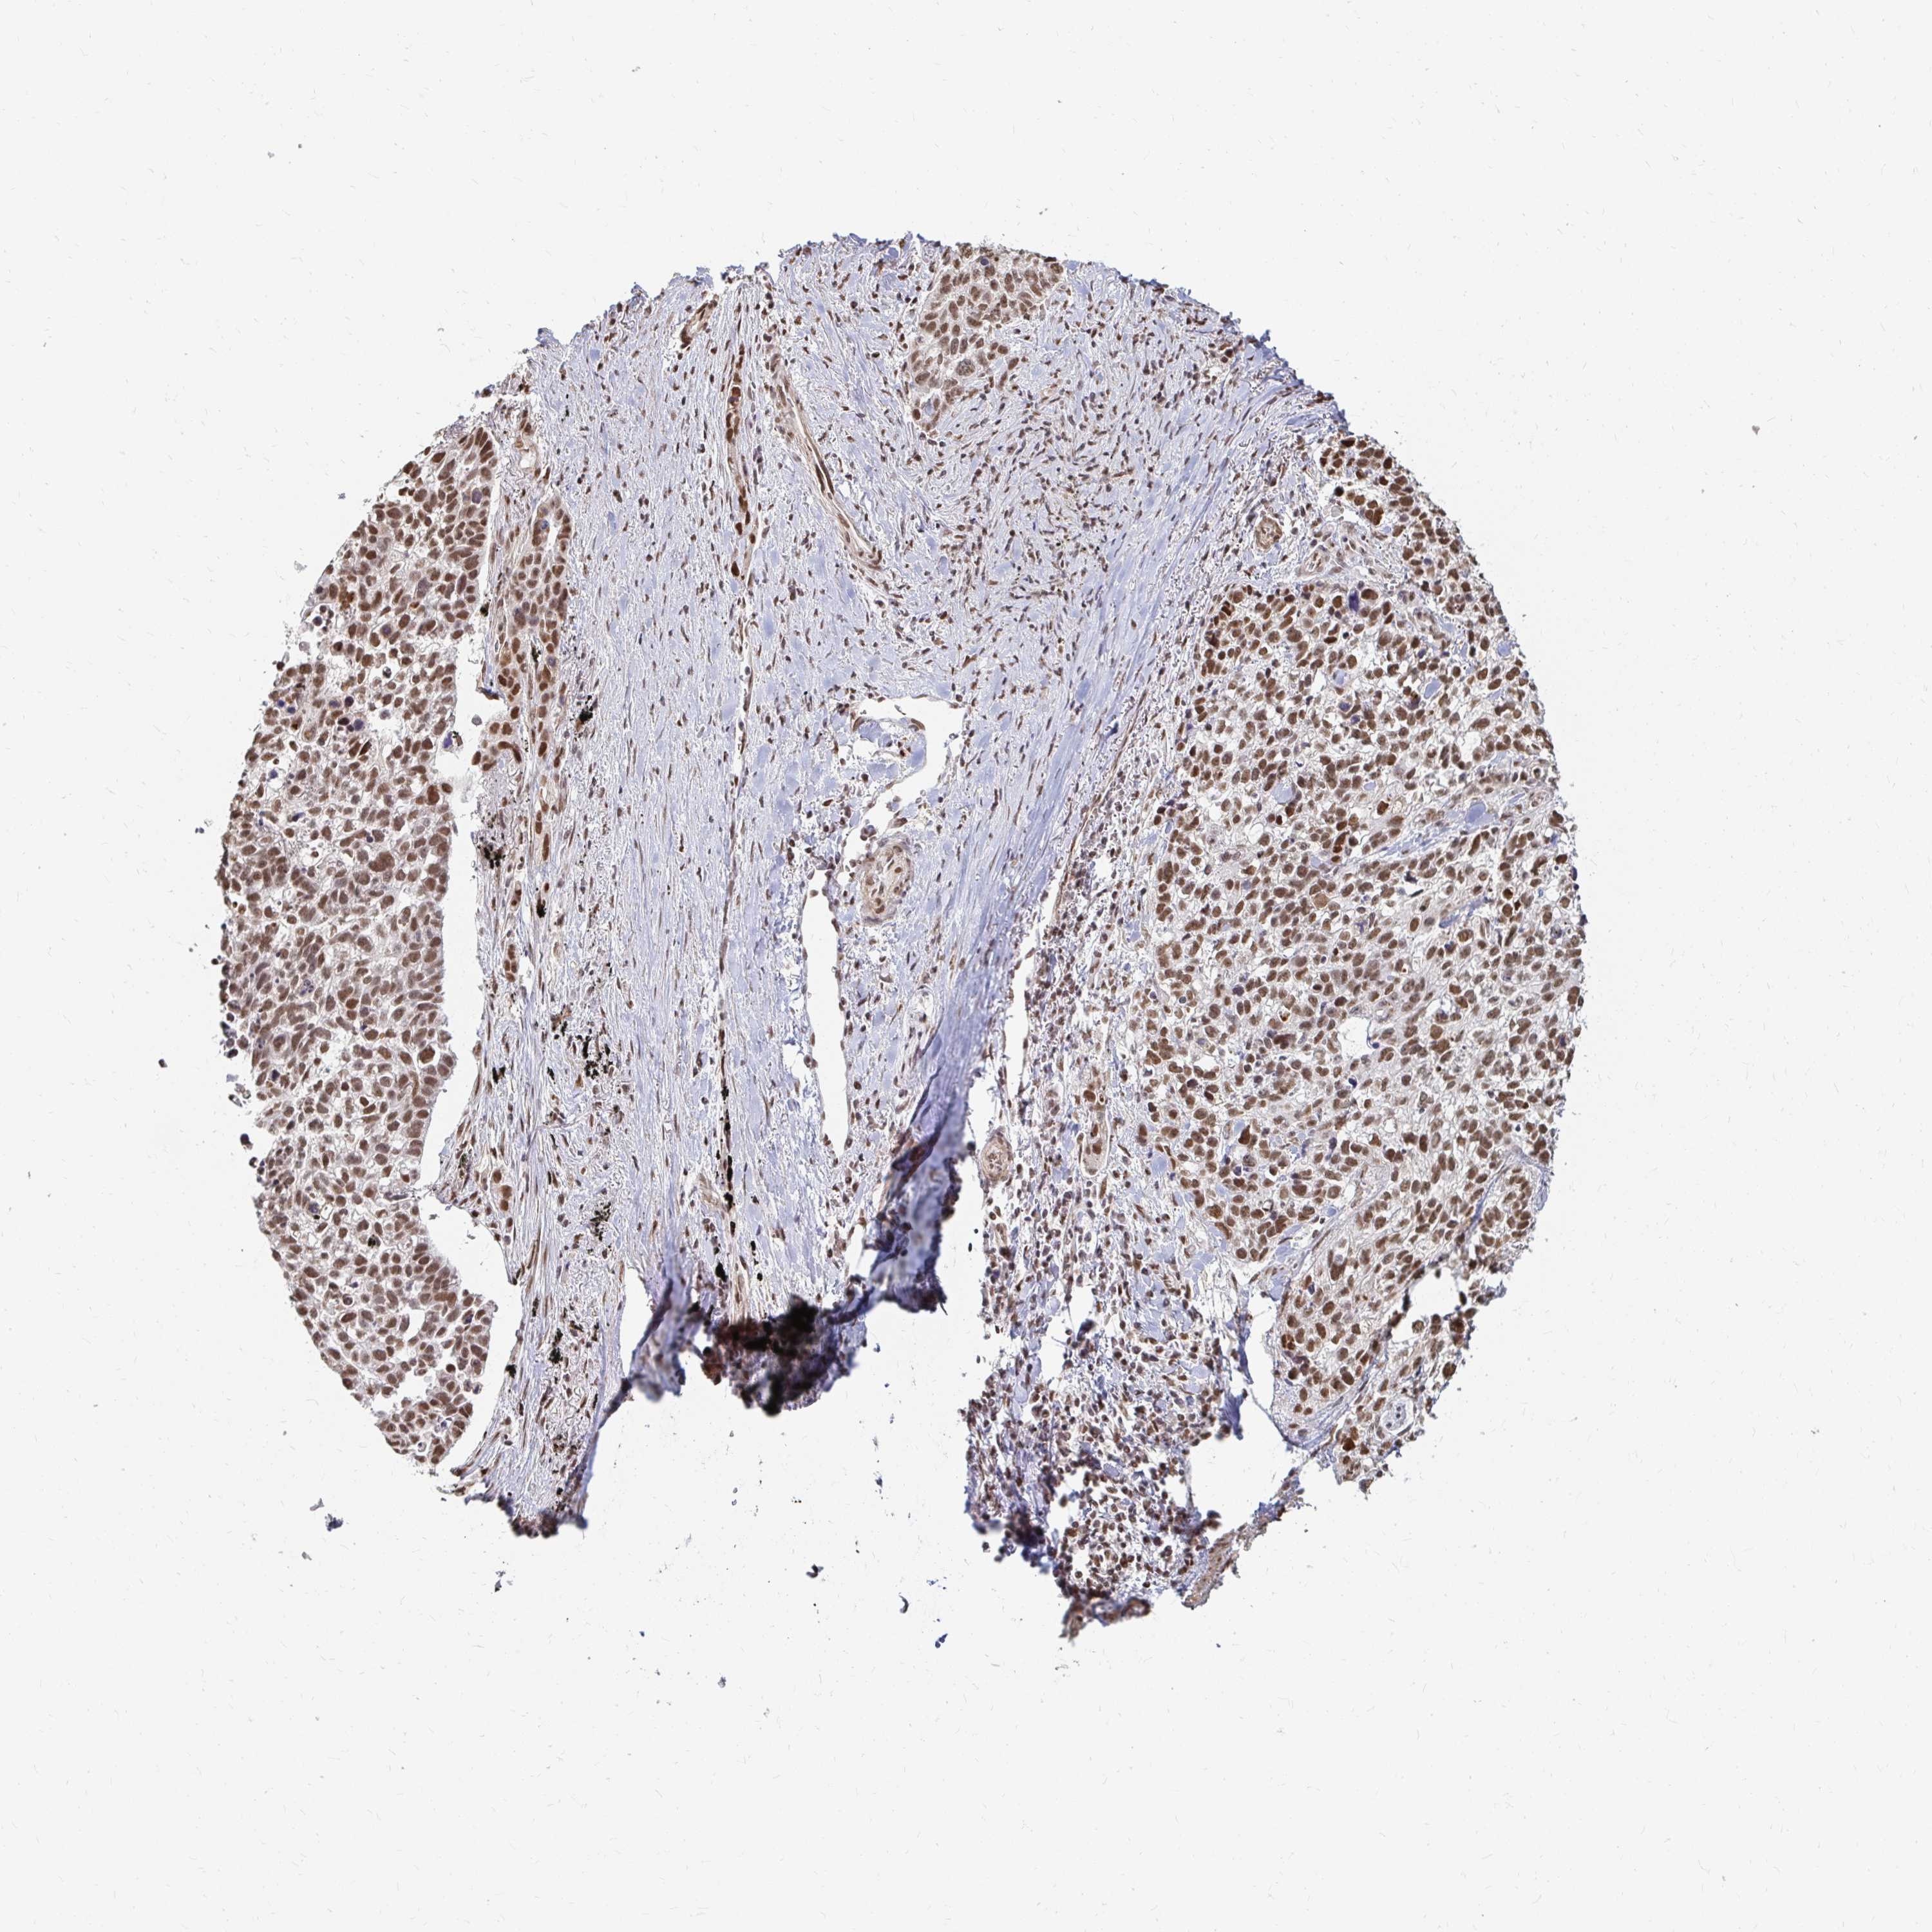

LUNG SQUAMOUS CELL CARCINOMA (TCGA) - Interactive survival scatter ploti

The Survival Scatter plot shows the clinical status (i.e. dead or alive) for all individuals in the patient cohort, based on the same data that underlies the corresponding Kaplan-Meier plots. Patients that are alive at last time for follow-up are shown in blue and patients who have died during the study are shown in red.

The x-axis shows the expression levels (FPKM) of the investigated gene in the tumor tissue at the time of diagnosis. The y-axis shows the follow-up time after diagnosis (years). Both axes are complimented with kernel density curves demonstrating the data density over the axes. The top density plot shows the expression levels (FPKM) distribution among dead (red) and alive patients (blue). The right density plot shows the data density of the survived years of dead patients with high and low expression levels respectively, stratified using the cutoff indicated by the vertical dashed line through the Survival Scatter plot. This cutoff is automatically defined based on the FPKM cutoff that minimizes the p-score. The cutoff can be changed by dragging the vertical line or by entering a cutoff value in the square labeled "Current cut-off".

Under the Survival Scatter plot the p-score landscape (black curve; left axis) is shown together with dead median separation (red curve; right axis). Dead median separation is the difference in median mRNA expression between patients who have died with high and low expression, respectively. It is calculated as follows: median FPKM expression of dead patients with high expression - median FPKM expression of dead patients with low expression. This is intended to aid the user in visually exploring custom cutoffs and the associated p-scores and dead median separation.

Individual patient data is displayed and can be filtered by clicking on one or more of the category buttons on the top of the page. Categories describing expression level and patient information include: high, low, alive, dead, female, male and tumor stages. The scale of the x-axis can be toggled between linear and log-scale by clicking on the "x log" button. Mouse-over function shows TCGA ID, patient information and mRNA expression (FPKM) for each patient.

& Survival analysisi

Kaplan-Meier plots summarize results from analysis of correlation between mRNA expression level and patient survival. Patients were divided based on level of expression into one of the two groups "low" (under cut off) or "high" (over cut off). X-axis shows time for survival (years) and y-axis shows the probability of survival, where 1.0 corresponds to 100 percent.

HNRNPU is not prognostic in Lung Squamous Cell Carcinoma (TCGA)

Best expression cut offi

Based on the FPKM value of each gene, patients were classified into two groups and association between prognosis (survival) and gene expression (FPKM) was examined. The best expression cut-off refers the FPKM value that yields maximal difference with regard to survival between the two groups at the lowest log-rank P-value. Best expression cut-off was selected based on survival analysis .

When clicking on this number, the vertical dashed line indicating cut-off, the interactive survival plot, and the Kaplan-Meier curve will be adjusted to show results based on the best expression cut-off.

: 136.2

Median expressioni

P scorei

Log-rank P value for Kaplan-Meier plot showing results from analysis of correlation between mRNA expression level and patient survival.

N/A

TCGA RNA samplesi

RNA-seq data is reported as average FPKM (number Fragments Per Kilobase of exon per Million reads), generated by the The Cancer Genome Atlas (TCGA) .

Normal distribution across the dataset is visualized with box plots, shown as median and 25th and 75th percentiles. Points are displayed as outliers if they are above or below 1.5 times the interquartile range. FPKM values of the individual samples are presented next to the box plot.

Average pTPM 163.2

Number of samples 489